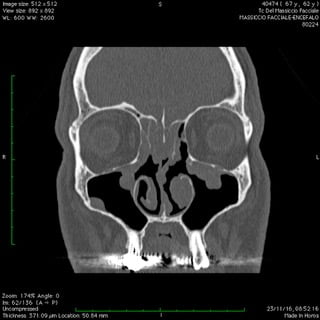

Anche nelle sinusiti la peculiare morfologia anatomica delle strutture coinvolte, cavità ossee, consente nella maggior parte dei casi latenze di esordio molto ritardate rispetto il primitivo insorgere patologico palesandosi così in avanzate fasi di compromissione .

Nelle forme croniche, cioè di malattia stabile nel tempo, i seni paranasali diventano “ siti di decantazione”, ovvero di ristagno e moltiplicazione,per germi di vario genere dando vita così ad un persistente primario serbatoio contaminante sia le vie aeree che quelle digestive.